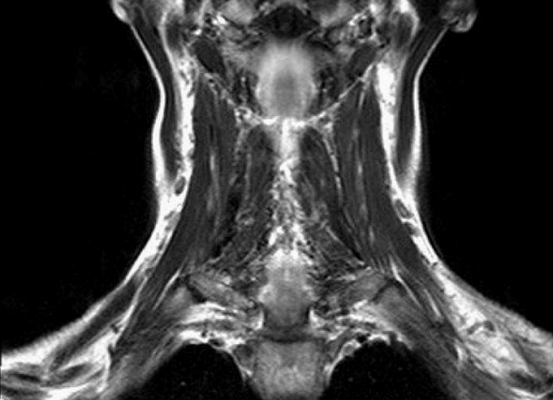

Магнитно-резонансная томография указанной области, вариант нормы

А - лимфаденопатия, В - зоб щитовидной железы

Магнитно-резонансная томография позволяет получить подробные характеристики пальпируемого образования шеи. По результатам диагностики врач дифференцирует:

Результат МР-сканирования мягких тканей шеи

Туберкулезный лимфаденит на снимке МРТ